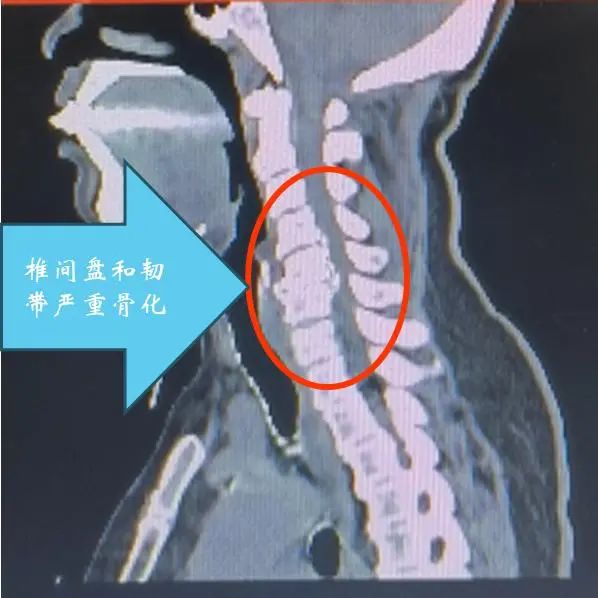

脊柱退变与畸形外科主任魏劲松教授为患者安排住院和详细检查。检查结果病情严重,在颈椎的第三到五节之间,有明显的已经钙化的病变椎间盘和韧带挤压神经,神经被挤得只剩下原来直径的四分之一,随时有彻底瘫痪的风险。这种情况下,只有将颈椎的部分椎体切除,才能解除神经压迫。然而这种手术不但风险巨大,而且要考虑将颈椎的椎体切除以后,如何替代原来的椎骨?通过与患者的仔细沟通,结合患者的病情,魏劲松教授决定采用3D打印的颈椎人工椎体置换手术来治疗患者的疾病。